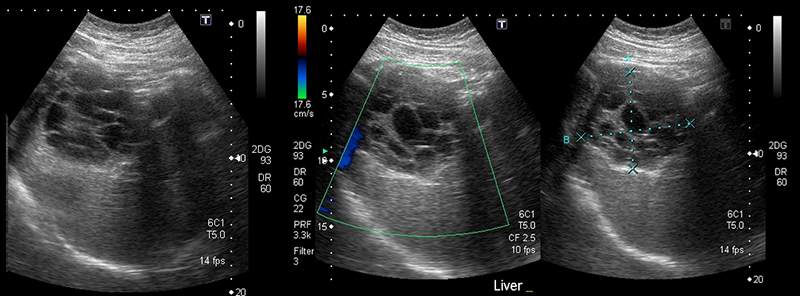

Figure 24A. Large pyogenic liver abscess with heterogenous material swirling inside the lesion, and “dirty shadowing.”

Figures 24B & 24C. Large pyogenic liver abscess with heterogenous material swirling inside the lesion, measuring >11cm in the long dimension (B) and >5cm in the shorter dimension (C).